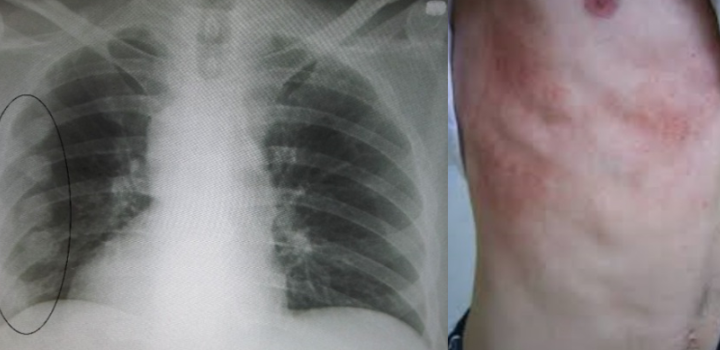

- 붓기와 멍: 외상에 의한 경우 부종과 멍자국이 생기기도 함

갈비뼈 금간 진단 방법

갈비뼈 금간 여부는 병원에서 다음과 같은 검사를 통해 진단합니다:

- 흉부 X-ray 촬영